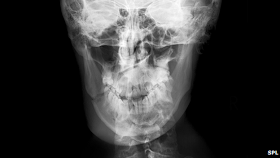

Όπως αναφέρουν οι ερευνητές στην επιθεώρηση Biological Reviews, το πρόσωπο και οι γνάθοι αυτών των προγόνων μας ήταν ισχυρότερα στις περιοχές που είναι πιθανότερο να δεχθούν πλήγμα με γροθιά.

«Είναι οι ίδιες περιοχές του κρανίου που παρουσιάζουν τις μεγαλύτερες διαφορές ανάμεσα σε άνδρες και γυναίκες, τόσο στους αυστραλοπίθηκους όσο και στους ανθρώπους» λέει ο Ντέιβιντ Κάριερ του Πανεπιστημίου της Γιούτα στο Σολτ Λέικ Σίτι, πρώτος συγγραφέας της δημοσίευσης. «Με άλλα λόγια, τα ανδρικά πρόσωπα διαφέρουν από τα γυναικεία επειδή τα τμήματα του κρανίου που μπορεί να υποστούν κάταγμα στους τσακωμούς είναι μεγαλύτερα στους άνδρες» εξηγεί.

The jaw bone is frequently fractured in fist fights and was strengthened in some of our evolutionary ancestors.